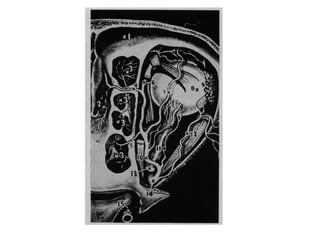

ANATOMIE: VASCULARISATIONVASCULARISATION

1. Artère de la sous cloison - 2. Artère ethmoïdale antérieure - 3. Lame criblée –

4. Artères ethmoïdales postérieures - 5. Artère sphénopalatine - 6. Foramen

Sphénopalatin - 7. Artères Postéro Latérales - 8. Artère Maxillaire interne - 9.

Artère Palatine